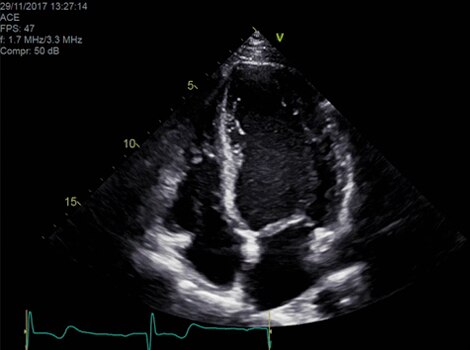

Diagnosis and Risk Assessment

Diagnosis typically involves assessment for ECG abnormality and assessment of cardiac structure, function and possible cause. Guidelines suggest use of echocardiography due to its widespread availability, but other non-invasive imaging modalities can be used. In certain cases, invasive monitoring provides useful information for patients with persistent symptoms. Biomarkers provide helpful information about progression of disease. 4

Vivid™ Family Cardiac Ultrasound with Automated Quantification

Assess left ventricular function and cardiac performance with clarty,improving clinical confidence.Read More